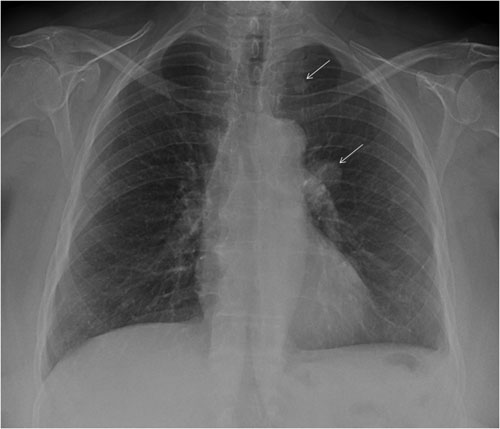

Las figuras 1, 2 y 3 ilustran ejemplos de signo, hallazgo y patrón.

Figura 2. Ejemplo de hallazgo. Se ven dos nódulos pulmonares encontrados de forma casual en un estudio preoperatorio. Correspondían a metástasis de un cáncer de colon no conocido.